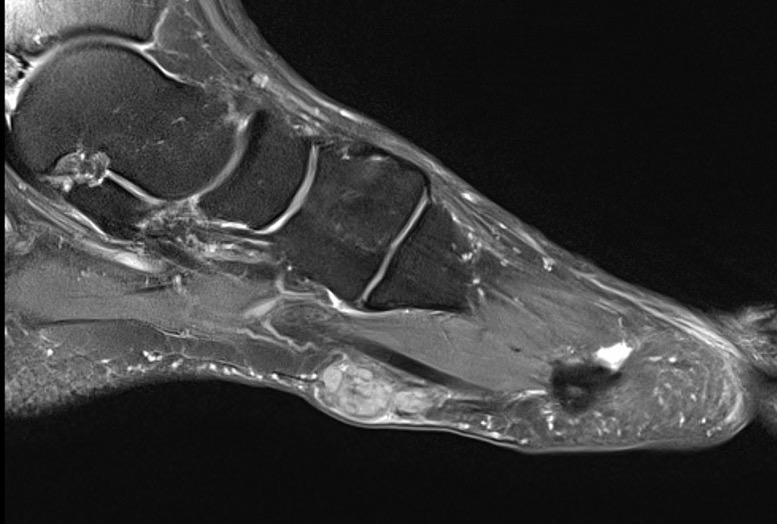

MRI

Focal oval shaped lesions within the plantar fascia